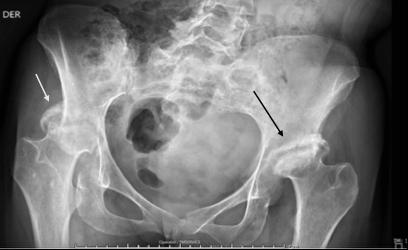

If you like it,why not share it...

Share with a colleague today

Turn static files into dynamic content formats.

Create a flipbook

EMJ 9.4 2024 by European Medical Journal - Issuu